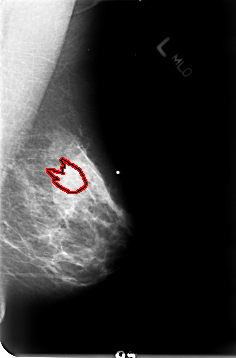

B_3023_1.LEFT_CC

LEFT_CC LINES 4696 PIXELS_PER_LINE 3072 BITS_PER_PIXEL 12 RESOLUTION 50 OVERLAY

FILE: B_3023_1.LEFT_CC.OVERLAY

TOTAL_ABNORMALITIES 1

ABNORMALITY 1

LESION_TYPE MASS SHAPE IRREGULAR-ARCHITECTURAL_DISTORTION MARGINS OBSCURED-ILL_DEFINED-SPICULATED

ASSESSMENT 4

SUBTLETY 3

PATHOLOGY MALIGNANT

TOTAL_OUTLINES 1

BOUNDARY